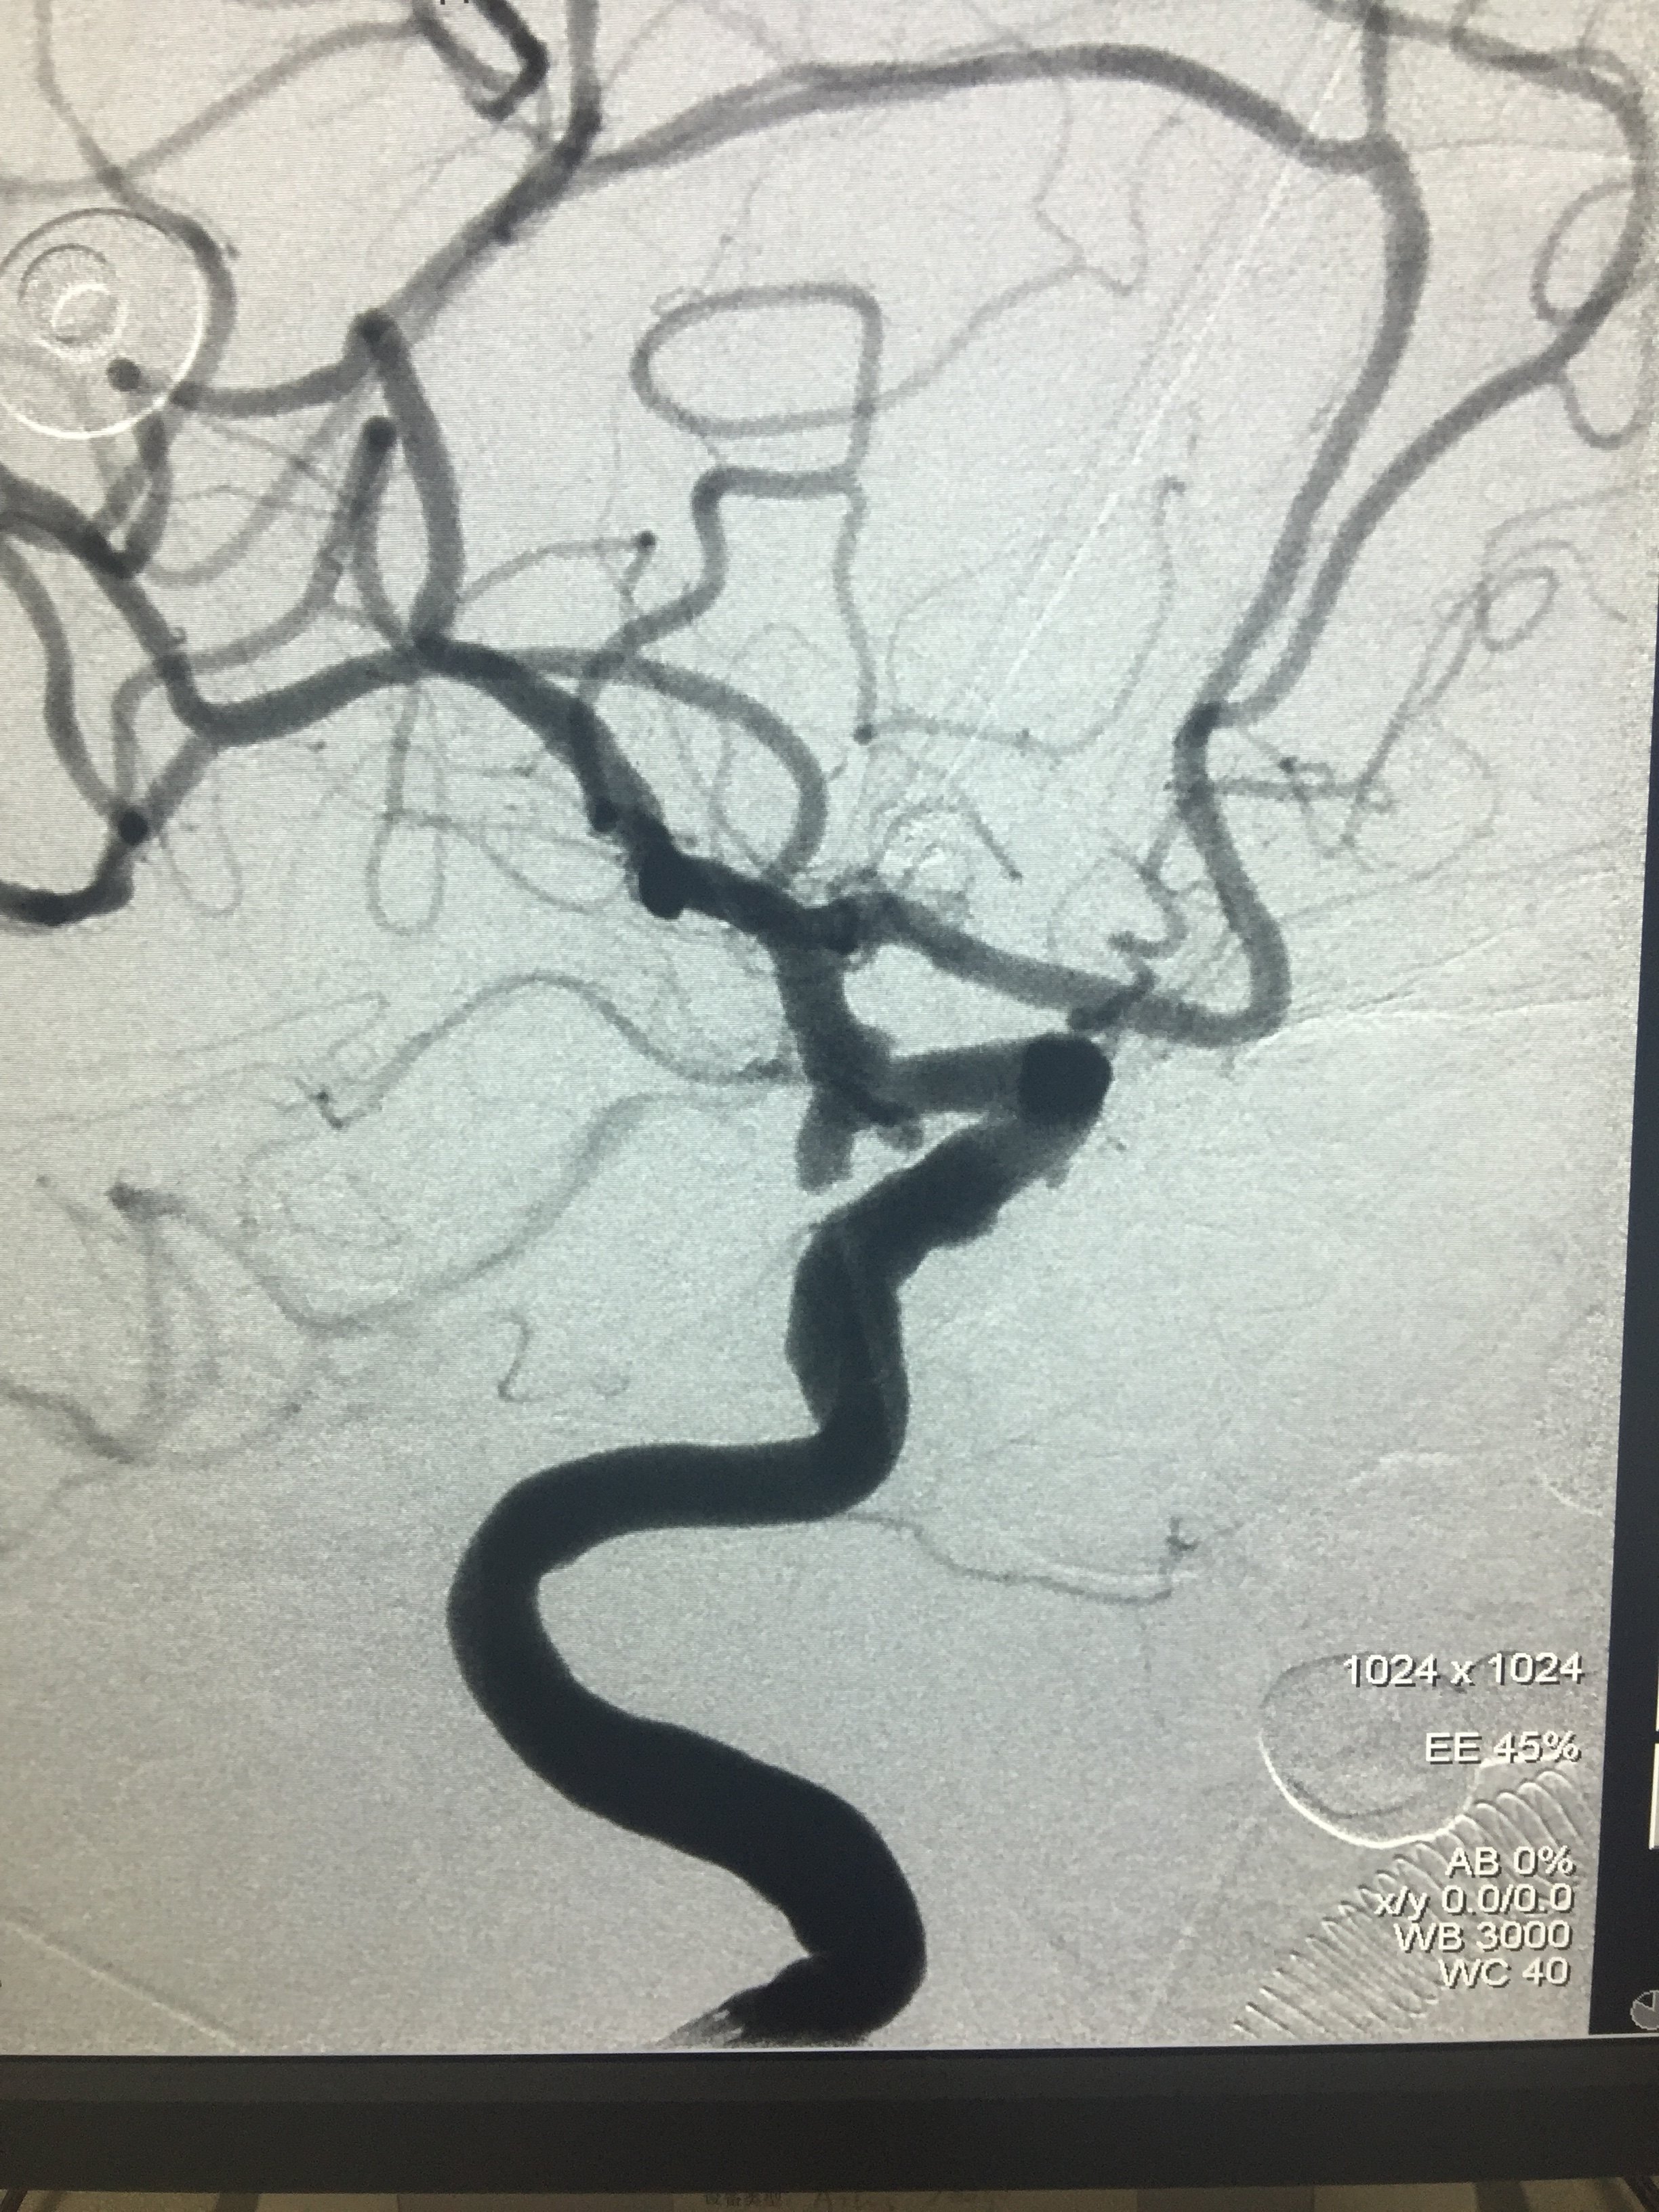

病例六:右侧后交通多发动脉瘤

1534032365.png

支架辅助栓塞